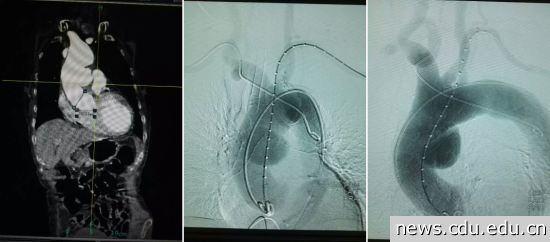

接受手术的是一名近80岁女性患者,该患者28岁即确诊类风湿性关节炎,长期受病痛折磨不得不每日口服激素及洛索洛芬钠抗炎镇痛治疗至今,患者在外院及附属医院确诊冠心病、主动脉瓣重度关闭不全、慢性心力衰竭、2型糖尿病,高血压病,脑梗塞、慢性肾功能不全等多系统危重疾病。患者多次因胸闷胸痛不适住院治疗,并曾因诱发恶性心律失常行电击复律,几度被告知病危。2016年4月,患者因胸痛来院就诊,CT血管造影术提示“升主动脉夹层动脉瘤伴升主动脉瘤样扩张,瘤壁菲薄,瘤体呈现囊袋状,长径约4cm,对周围大血管压迫效应明显”,病情极其危重,一旦动脉瘤破裂就会发生心包填塞、心跳骤停或失血性猝死。

4月29日,介入手术在介入室如期进行,术中探查见患者双侧股动脉多发粥样硬化斑块,通路建立困难,与患者家属沟通征得同意后,迅速改髂动脉入路建立血管通道,置入导管造影明确定位,交换导丝置入支架。在治疗团队的努力和精准定位下,支架释放一蹴而就,再次造影见位置准确,破口封闭良好,瘤体显影明显浅淡,观察后再次造影,瘤体几近消失。